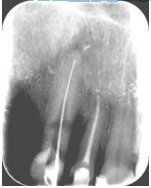

24.

Przedstawiony na rentgenogramie obraz zęba jest charakterystyczny dla: